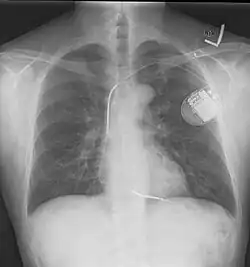

Konventioneller ICD im Röntgenbild, die Schockelektrode wurde über die linke V. subclavia eingebracht. Es handelt sich um eine Dual-Coil-Elektrode. Die erste Schockspule befindet sich auf Höhe der oberen Hohlvene, die zweite in der rechten Hauptkammer.

Ein ICD besteht im Prinzip aus zwei Komponenten. Einerseits dem ICD-Gerät, das aus der Steuerung, einer Batterie und einer Elektrode besteht, und einer venösen Elektrode, die in der rechten Herzkammer verankert wird. Der ICD wird unter der Haut vor oder in dem linken Brustmuskel implantiert. Der Diagnostikteil erkennt durch permanente EKG-Ableitung behandlungsbedürftige Störungen, der Stimulationsteil löst daraufhin den Stromstoß aus. Beim Schock wird ein elektrisches Feld aufgebaut.[5] Bei modernen Geräten kann dieses entweder zwischen der venösen Elektrode und dem Gehäuse des ICD-Geräts aufgebaut werden oder aber bei Verwendung sogenannter Dual-Coil-Elektroden (wie auf dem abgebildeten Röntgenbild) zwischen zwei getrennten Spulen einer venösen Elektrode. So kann je nach individueller Anatomie das elektrische Feld mit dem Ziel optimiert werden, möglichst viel Herzmuskelgewebe im elektrischen Feld zu erfassen.[6]